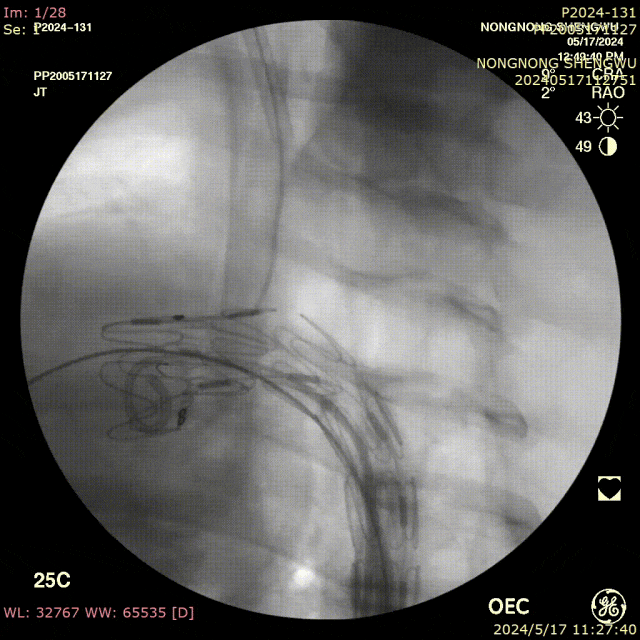

优势:

破膜操作起始于主动脉主腔,完全避开分支血管,避免分支损伤;

前盘稳定摁住覆膜支架,防止破膜针滑动;

穿刺方向垂直于支架表面,确保精准、圆整的破口。